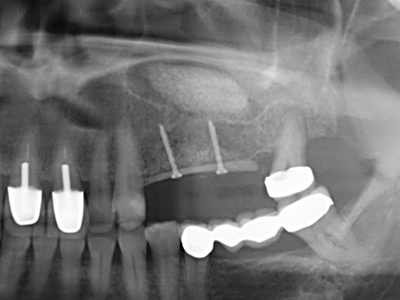

Abb. 11: Das postoperative OPTG veranschaulicht die vertikale Augmentation und Sinusbodenelevation.

Abb. 15: Die röntgenologische Ein-Jahres-Kontrolle zeigt stabile Verhältnisse des Knochenniveaus.